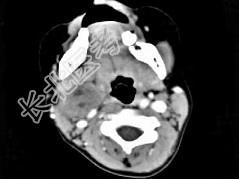

- 单项选择题女,4岁, 右侧颈部可扪及一包块约两个月,无热无痛, CT如图所示,最可能的诊断为 ( )

A、咽旁血管外皮瘤

B、咽旁副神经节瘤

C、咽旁脓肿

D、咽旁神经纤维瘤

E、咽旁小唾液腺混合瘤